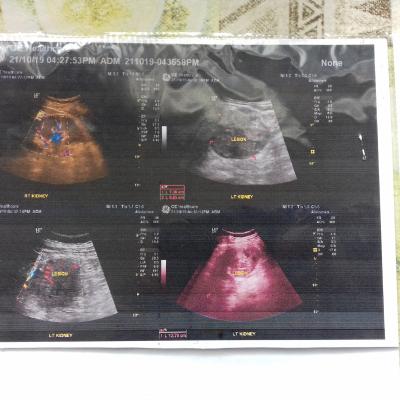

Здравствуйте. После нефрэктомии левый почки болить левая нога и яйца левая немного опухла. Так должно или что делать?

Здравствуйте! Боли в нижней конечности могут быть следствием вынужденного положения во время операции, надо показаться неврологу. А отёк левого яичка может быть связан с особенностями операции. Сделайте УЗИ органов мошонки, покажитесь урологу. Удачи!